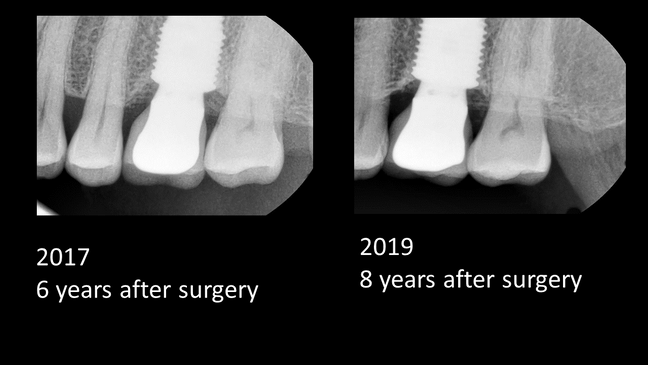

Extraction Like Defect [10 Years]

Left Maxillary, First Molar, Immediate Placement, One Stage

Operation Site: #26